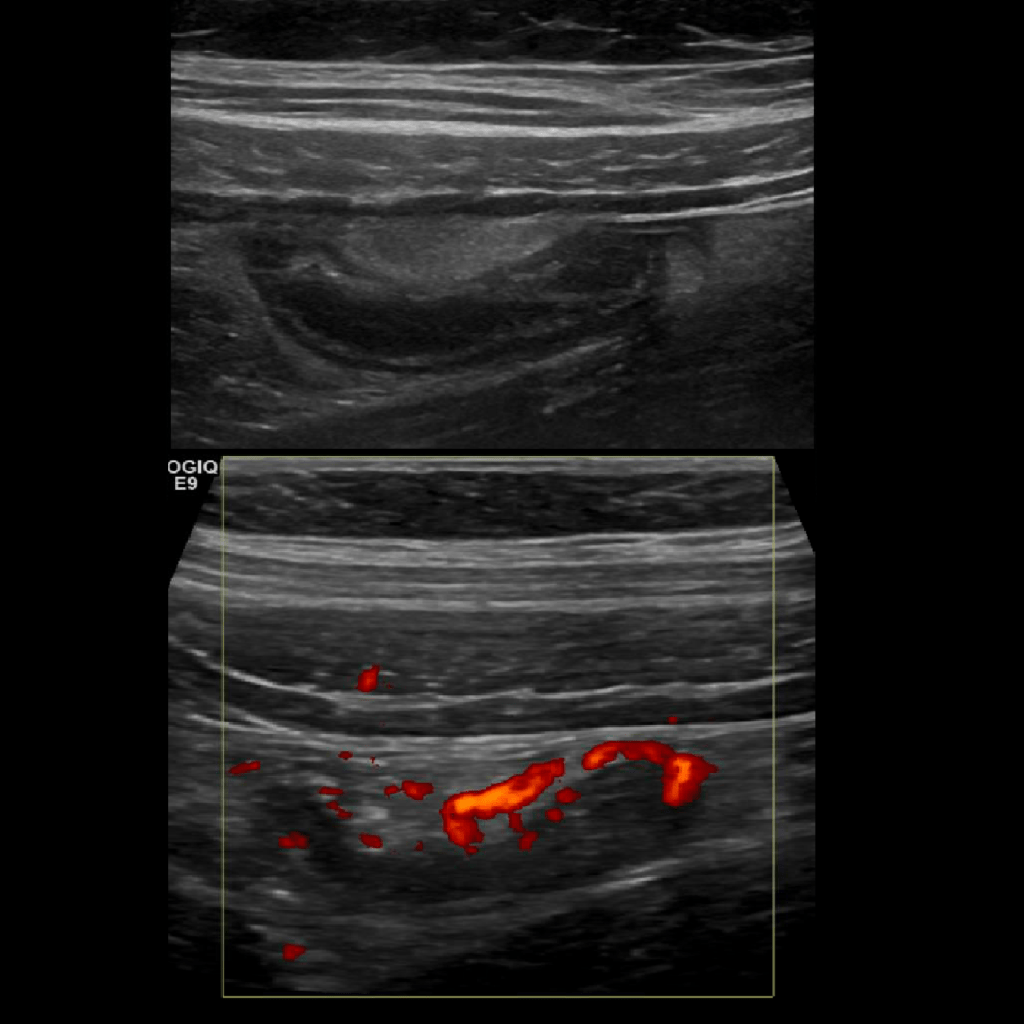

Appendicitis 11

Acute appendicitis with hyperemia and fat stranding.